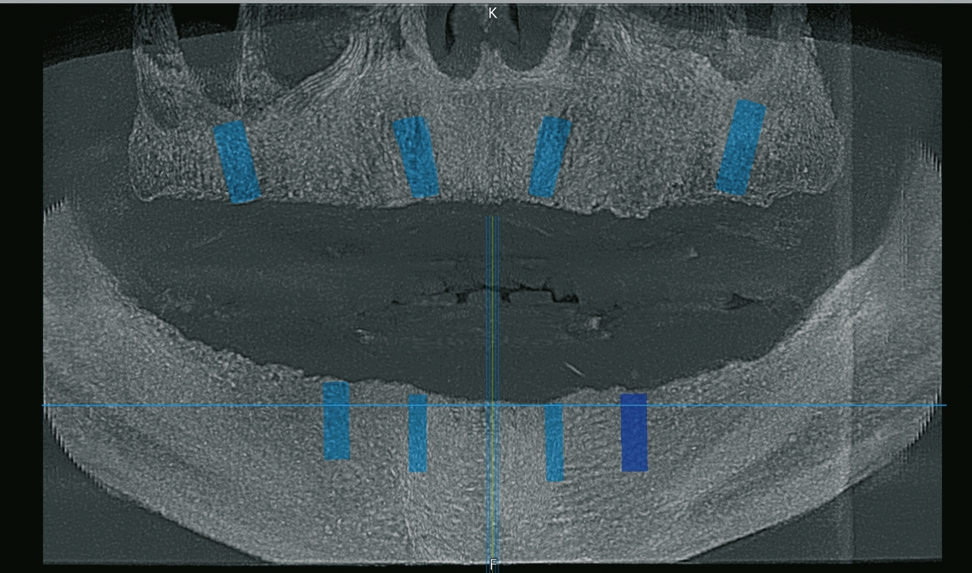

Der 49-jährige Patient trägt im Oberkiefer eine Prothese. Die Prothese im Unterkiefer hat ihn immer gestört, weswegen er diese schon länger nicht mehr getragen hat. Die Abbildungen 1 bis 3 zeigen den Ausgangsbefund. Während der Oberkiefer klinisch noch gut für Implantate geeignet erscheint, können im Unterkiefer schon Zweifel aufkommen. Bei genauerer Betrachtung des Oberkiefers in der Schichtaufnahme (OPG) kommt jedoch die Vermutung auf, dass der Knochen dünn sein könnte. Das war der Grund, warum wir vor der Implantation ein DVT erstellt haben.

Im vorgestellten Fall wurde die Planung über eine externe Software durchgeführt, die dann von der Firma C-Tech (Italien) übernommen wurde. Für den Patienten wurden im Vorfeld Prothesen hergestellt, welche im DVT mit eingebracht wurden, um eine entsprechende Planung der Soll-Position durchführen zu können.

Die Abbildungen 1 bis 3 zeigen die Ausgangssituation. Zuerst wurde nach der Herstellung einer Prothese eine Implantatplanung gemacht. In den Abbildungen 5 bis 7 zeigt sich die Herausforderung in diesem Fall: Geringe Platzverhältnisse für die Implantate im Knochen. Nachdem die erstellten Daten verschickt wurden, bekommen wir die Schablonen zurück (Abb. 8).

In Abbildung 12 ist die Einbringhilfe schön zu sehen. In Abbildung 13 kann man die relativ geringe Höhe der Schablone erkennen. Dadurch ist ein Implantieren auch im hinteren Bereich möglich. Gerne werden die Schablonen zu dick oder zu hoch gefertigt, so dass man schon ab dem 6er Bereich den Bohrer nicht mehr in die Schablone bekommt. Dann ist der Aufwand sehr groß, um damit zu implantieren. Aber hier ist dies erfreulicherweise möglich, da durch das C-Guide Konzept, eine ausreichende Führung der Bohrer gewährleistet ist. Trotz den niedrigen Hülsen ist eine Bohrführung gegeben! Nachdem nun alle Implantate eingebracht wurden, zeigt die klinische Kontrolle (Abb. 17) und auch das Abschlussbild im OPG (Abb. 18), dass die Implantate genau nach Planung gesetzt wurden (Abb. 19).